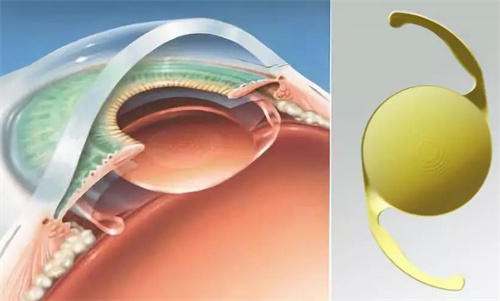

三焦点晶体:相比传统单焦点,可同时优化远、中、近视力,术后不用戴老花镜。

个性化方案:根据患者角膜状况、用眼习惯定制手术,比如喜欢看书或开车的老人,医生会调整晶体参数优化视觉结果。

严格术前评估:确保患者符合手术条件,降低术后眩光等风险。